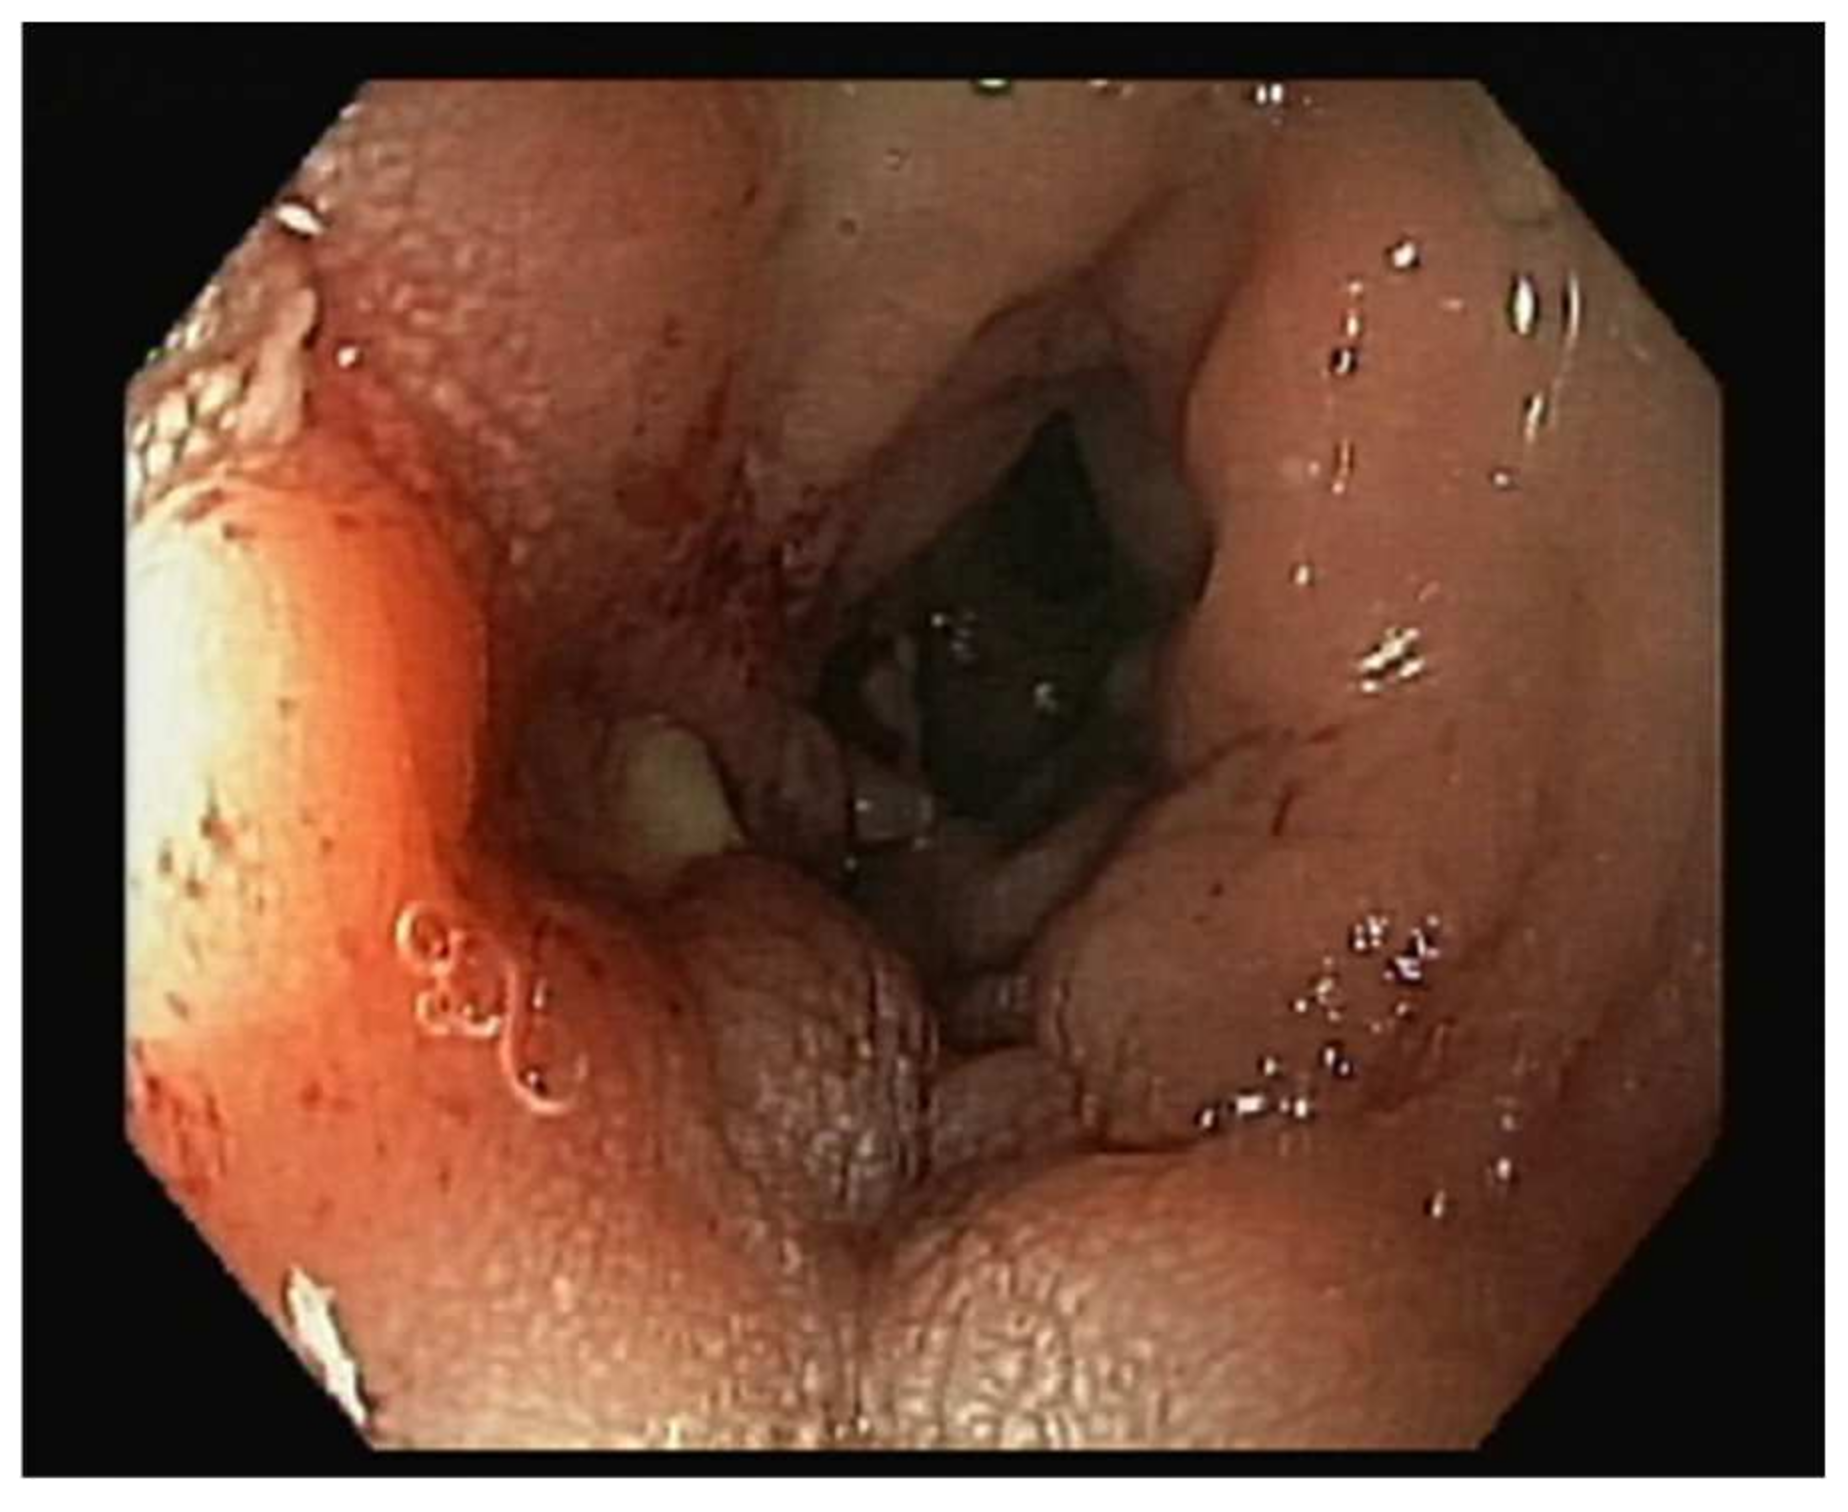

The patient was referred to the gastroenterology practice due to a routine faecal occult blood test that was positive and abnormal findings in the colonoscopy. She mentioned she had experienced vaginal bleeding in scarce quantities a few months prior, without other symptoms, namely changes in gastrointestinal habits, abdominal pain, bloating, haematochezia, weight loss, fever, or fatigue. The colonoscopy revealed inflammatory changes with a granular appearance in a significant part of the mucosal circumference in the sigmoid colon mucosa wall, approximately around 20 cm from the anal verge. There was a suspicion of a fistulous tract with purulent drainage (Figure 1) and that area was biopsied. The histopathological analysis of the biopsied areas showed chronic inflammatory unspecific colitis without malignant or premalignant changes and, therefore, a hypothesis of colonic ulcer or fistula was made.

Figure 1. Inflammatory changes in sigmoid colon mucosa wall around 20 cm from anal verge, with a granular appearance in a significant part of the mucosal circumference. There was a suspicion of a fistulous tract with purulent drainage that was biopsied.